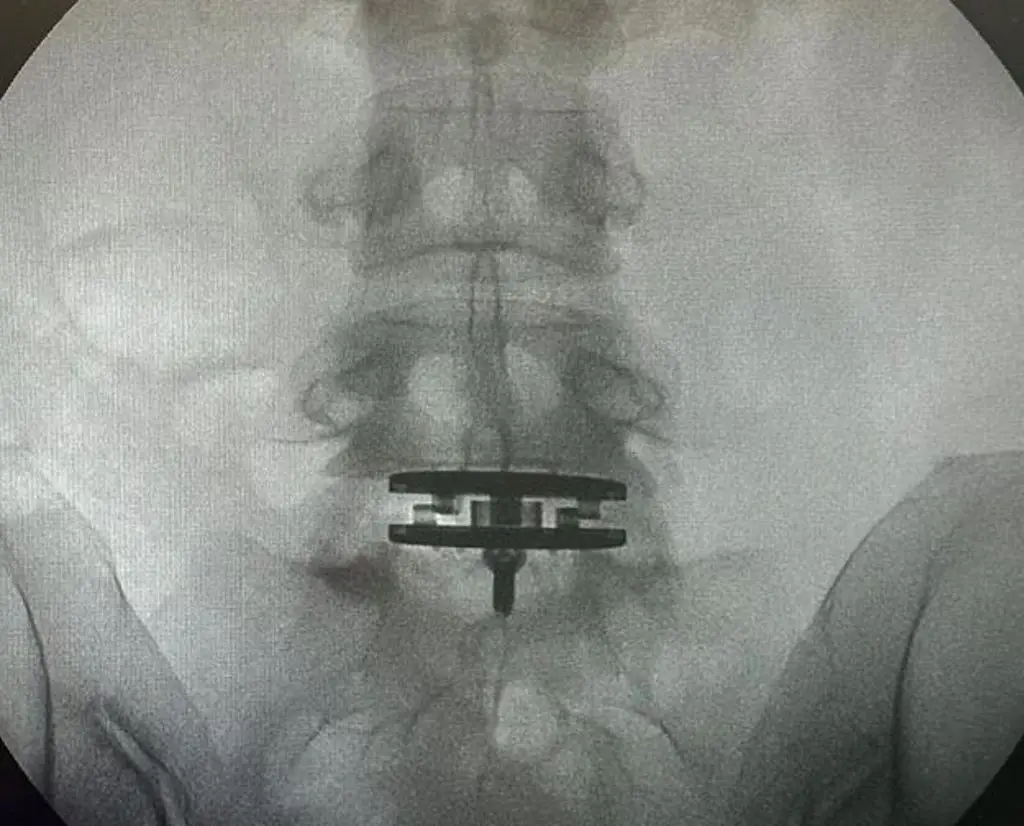

陳奕迅老婆徐濠縈2022年腰椎間盤手術(shù)后,狀態(tài)未明顯好轉(zhuǎn),打噴嚏都會引起劇痛,近日她再次接受手術(shù)。24日,徐濠縈曬出X光照片,可見腰椎接近骨盆的位置放入了儀器在治療。女兒康堤也為她打氣:“加油媽媽!”目前,手術(shù)結(jié)束,徐濠縈靜心休養(yǎng)。